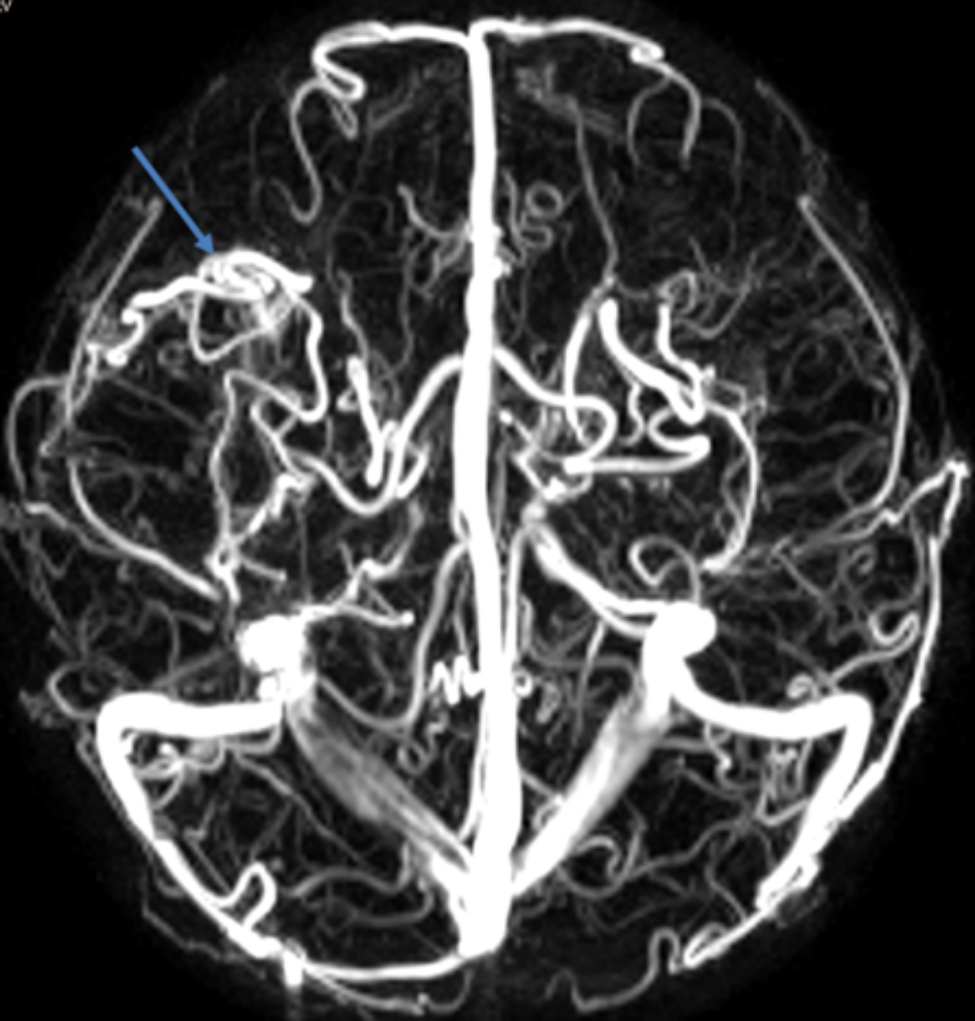

Fig. 3.

Non-contrast magnetic resonance imaging, artery and vein of the brain revealed multiple malformations of venous sinuses

Physical examination revealed cyanosis of nail beds, clubbed fingers, and abundant vascular networks on her face particularly upper eyelid and on her back (Fig. 1D and E). Her body mass index was 13.1. Arterial blood gas analysis revealed a pressure of arterial oxygen of 55 mmHg and an oxygen saturation of 87% of in the supine position. In laboratory investigations, we detected normal liver enzymes, renal function and ceruloplasmin; and increased serum lactate dehydrogenase (LDH), indirect bilirubin (IBIL), total bile acids (TBA), and glycocholic acid (GA) (Table 1). Coombs’ test was negative. Screening for metabolic diseases revealed no abnormalities. Contrast enhanced lung CT with vascular three-dimensional reconstruction and abdominal CT revealed increased pulmonary vascular bundles and bronchovascular bundles (Fig. 2A and B); increased diameter of the main PA (22 mm), left PA (16 mm), right PA (15 mm) and ascending aorta (AA, 14 mm) (Fig. 2C); and left hepatic venous-left portal venous shunt (Fig. 2D and E; Table 2). Doppler echocardiography revealed increased diameter of aortic and pulmonary artery, and mild tricuspid and pulmonary valve regurgitation with a tricuspid regurgitation pressure gradient (TRPG) of 19.7 mmHg. Transthoracic contrast echocardiography (TTCE) was positive with grade 3/3 (bubble appearing in the left ventricle after 5 cardiac cycles). Pulmonary perfusion scan showed radioactivity in the brain, bilateral kidneys, liver, and spleen, suggesting the existence of intrapulmonary shunt due to PAVMs (shunt: 12.8%, Table 2). Abdominal and portal vein system color doppler ultrasound revealed a tortuous and dilated tubular structure connecting the left hepatic vein with the left branch of portal vein in liver suggesting left hepatic venous-left anterior branch of portal venous shunt (Table 2), and normal liver elasticity (4.64kpa). Interventional arteriography was performed, but no intrahepatic arteriovenous shunt was found. Non-contrast magnetic resonance imaging, artery and vein of the brain revealed multiple malformations of venous sinuses (Fig. 3). Using trio whole-exome sequencing (WES), we did not identify a variant [including an intronic variant that is > 15 bp from the exon boundaries (which are unlikely to affect messenger RNA splicing)], or a large genomic deletion associated with vascular malformations (including ENG, ACVRL1, SMAD4, GDF2, RASA1, and EPHB4 genes). The other results of auxiliary examination are summarized in Tables 1 and 2.